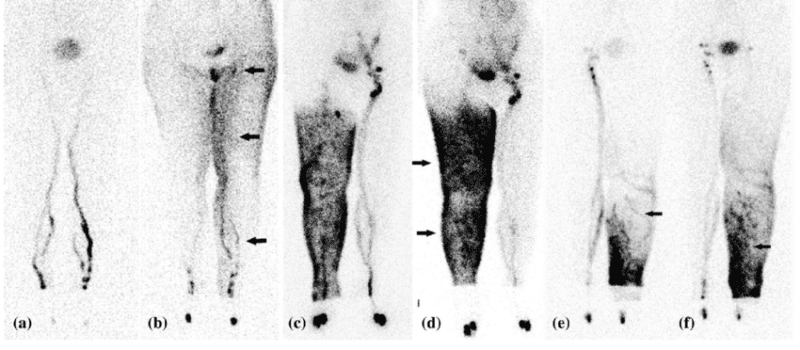

6. Lymphoscintigraphy

A lymphoscintigraphy is a scan that is part of nuclear medicine tests, and it is specifically used to detect any interruption within the lymphatic system.

The test is done in the specific clinic, and no recovery is needed for it. The procedure consists of injecting a radioactive liquid either in the feet or hands and with a specific camera, detecting the movement of the liquid within the body. We would expect the liquid to move within a certain timing and pathway along the lymphatic system. If that doesn’t happen, this test can give a good understanding if anything is not functioning with the lymphatic system.